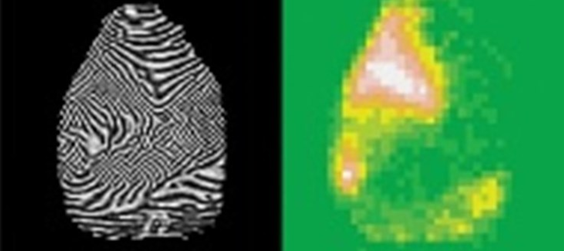

Los resultados de esta investigación, que han sido publicados en la revista científica Schizophrenia Bulletin, han demostrado, mediante la utilización de algoritmos avanzados de inteligencia artificial, la posibilidad de discernir entre qué huellas dactilares son de una persona con esquizofrenia y cuáles son de una persona sana, con una fiabilidad del 70%. De este modo, la investigación revela el uso de la huella dactilar como un marcador de riesgo para la detección de esta patología mental de forma útil y fiable. Además, permitía esta detección, tanto de manera inmediata, como para identificar el futuro desarrollo de esta enfermedad. Más si cabe, teniendo en cuenta que la huella dactilar permanece de forma inmutable durante toda nuestra vida.

En relación a la metodología de este procedimiento, éste parte de un escaneo de los dedos del paciente. Concretamente, se demostró que el testeo simultaneo de los dedos pulgar izquierdo, índice y corazón otorgaba la fiabilidad más alta a la hora de detectar la presencia de esquizofrenia en el individuo de estudio, con un 70% de precisión. Posteriormente, a través de un algoritmo, se procesan estas imágenes dactilares con patrones de alta complejidad que permiten determinar la probabilidad de riesgo de padecer la enfermedad. De esta manera, por medio de un rápido procedimiento se puede avanzar la presencia de esquizofrenia, incluso antes de que se manifieste en el paciente.